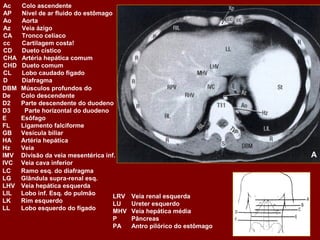

Ac Colo ascendente AP Nível de ar fluido do estômago Ao Aorta Az Veia ázigo CA Tronco celíaco cc Cartilagem costa! CD Dueto cístico CHA Artéria hepática comum CHD Dueto comum CL Lobo caudado fígado D Diafragma DBM Músculos profundos do De Colo descendente D2 Parte descendente do duodeno D3 Parte horizontal do duodeno E Esôfago FL Ligamento falciforme GB Vesícula biliar HA Artéria hepática Hz Veia IMV Divisão da veia mesentérica inf. A IVC Veia cava inferior LC Ramo esq. do diafragma LG Glândula supra-renal esq. LHV Veia hepática esquerda LIL Lobo inf. Esq. do pulmão LRV Veia renal esquerda LK Rim esquerdo LU Ureter esquerdo LL Lobo esquerdo do fígado MHV Veia hepática média P Pâncreas PA Antro pilórico do estômago

Ac Colo ascendente AP Nível de ar fluido do estômago Ao Aorta Az Veia ázigo CA Tronco celíaco cc Cartilagem costa! CD Dueto cístico CHA Artéria hepática comum CHD Dueto comum CL Lobo caudado fígado D Diafragma DBM Músculos profundos do De Colo descendente D2 Parte descendente do duodeno D3 Parte horizontal do duodeno E Esôfago FL Ligamento falciforme GB Vesícula biliar HA Artéria hepática Hz Veia IMV Divisão da veia mesentérica inf. IVC Veia cava inferior B LC Ramo esq. do diafragma LG Glândula supra-renal esq. LHV Veia hepática esquerda LIL Lobo inf. Esq. do pulmão LRV Veia renal esquerda LK Rim esquerdo LU Ureter esquerdo LL Lobo esquerdo do fígado MHV Veia hepática média P Pâncreas PA Antro pilórico do estômago

Ac Colo ascendente AP Nível de ar fluido do estômago Ao Aorta Az Veia ázigo CA Tronco celíaco cc Cartilagem costa! CD Ducto cístico CHA Artéria hepática comum CHD Ducto comum CL Lobo caudado fígado D Diafragma DBM Músculos para vertebrais De Colo descendente D2 Parte descendente do duodeno D3 Parte horizontal do duodeno E Esôfago FL Ligamento falciforme GB Vesícula biliar HA Artéria hepática Hz Veia IMV Divisão da veia mesentérica inf. C IVC Veia cava inferior LC Ramo esq. do diafragma LG Glândula supra-renal esq. LHV Veia hepática esquerda LIL Lobo inf. Esq. do pulmão LRV Veia renal esquerda LK Rim esquerdo LU Ureter esquerdo LL Lobo esquerdo do fígado MHV Veia hepática média P Pâncreas PA Antro pilórico do estômago

Ac Colo ascendente AP Nível de ar fluido do estômago Ao Aorta Az Veia ázigo CA Tronco celíaco cc Cartilagem costa! CD Dueto cístico CHA Artéria hepática comum CHD Dueto comum CL Lobo caudado fígado D Diafragma DBM Músculos profundos do De Colo descendente D2 Parte descendente do duodeno D3 Parte horizontal do duodeno E Esôfago FL Ligamento falciforme GB Vesícula biliar HA Artéria hepática Hz Veia IMV Divisão da veia mesentérica inf. D IVC Veia cava inferior LC Ramo esq. do diafragma LG Glândula supra-renal esq. LHV Veia hepática esquerda LIL Lobo inf. Esq. do pulmão LRV Veia renal esquerda LK Rim esquerdo LU Ureter esquerdo LL Lobo esquerdo do fígado MHV Veia hepática média P Pâncreas PA Antro pilórico do estômago